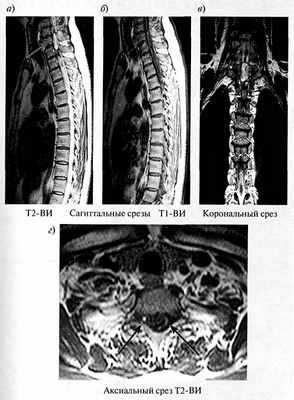

Рис. 1.34. Постравматическая сирингомиелия. МРТ

При магнитно-резонансной томографии выявляется посттравматическая сирингогидромиелическая полость с четкими ровными контурами, имеющая вид умеренно гиперинтенсивного на Т2-ВИ и гипоинтенсивного на Т1-ВИ очага в структуре спинного мозга (толстые стрелки), вызывающая его ложное утолщение. Вещество спинного мозга на данном уровне представлено тонкой полоской (тонкая стрелка)